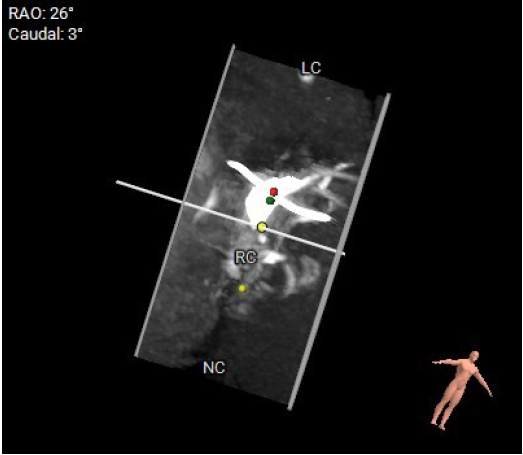

影像分析

生物瓣金属内径28.9mm

无论开展任何瓣位的瓣中瓣手术前,都应先明确原外科生物瓣的类型和型号,不同类型的外科生物瓣都具有不一样的透视下特征,如果透视性差的情况下,术中需要结合TEE协助定位。同样,原外科生物瓣的尺寸也对介入瓣尺寸的选择至关重要。

本例患者15年前因三尖瓣增厚伴重度反流,接受31#三尖瓣生物瓣置换。该类型的外科生物瓣在影像下透视性差,术中难以清晰捕捉其形态和位置。同时,其右心室狭小,留给介入瓣操作的空间有限,使得本次手术难度升级。宁波市第一医院心外科励峰主任团队凭借丰富的瓣膜外科手术经验,成功经右房途径TTViV植入一枚29#的J-Valve瓣膜。J-Valve经心尖介入瓣膜系统,在治疗生物瓣衰败的改为患者中行瓣中瓣植入术可以取得良好的临床效果。其独特的定位件设计,能够准确牢固地锚定在原生物瓣的瓣脚上,降低瓣膜移位的发生率。术后,患者三尖瓣跨瓣压差、反流及右房压均明显改善,即刻获益。